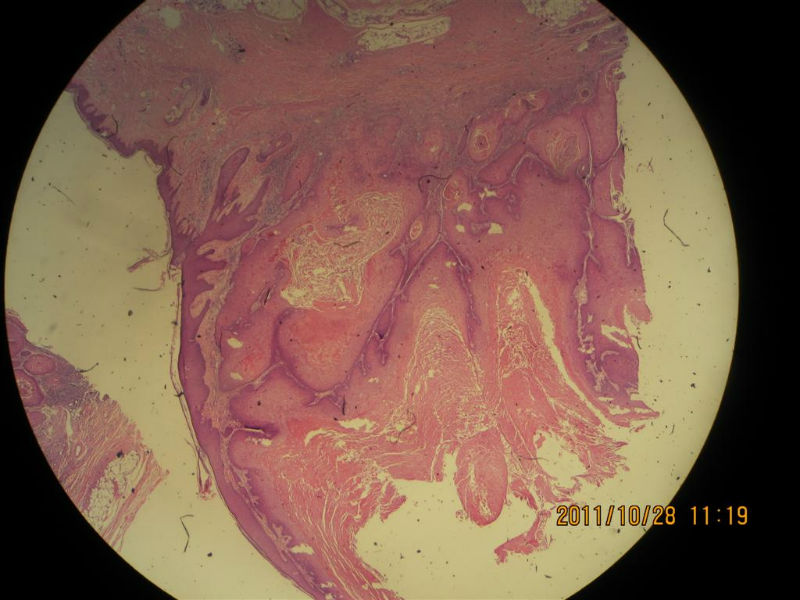

女性,71岁,右前臂肿物。角化棘皮瘤还是高分化鳞癌?

• 女性,71岁,右前臂肿物。角化棘皮瘤还是高分化鳞癌?图1

图1

不知道肿物的生长速度怎样?活动度?低倍看火盆样外观、唇样边缘,底部较平整,无明显突破。更趋向于角化角化棘皮瘤。

低倍镜见表皮呈火山口样,内充满角质团块,周边上皮增生呈衣领样,底部表皮增生呈假上皮瘤样,上皮角不规则延伸至真皮,真皮大量炎细胞浸润.

低倍镜下看符合角化棘皮瘤